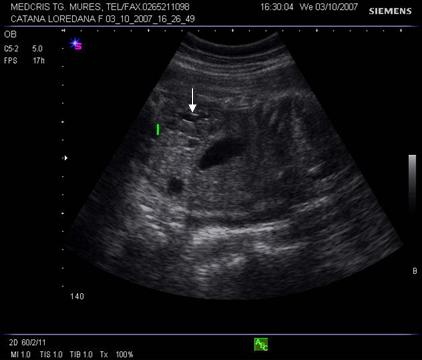

Fig. nr. 280. Formatiune anecogena intrabdominala, posibil hidronefroza , la un fat cu anamnios, retard major de crestere intrauterina RCIU si presupus sindrom genetic

Fig. nr. 281. Acelasi fat cu anamnios si RCIU, cu os nazal relativ scurt